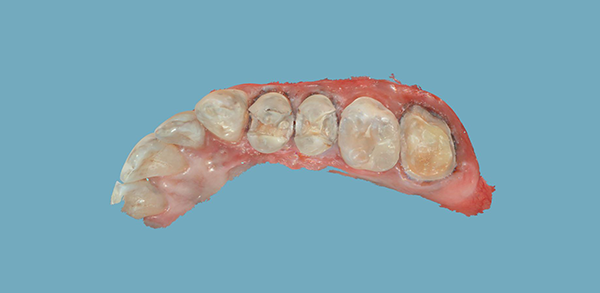

Inlays and crown were prepped, and the rubber dam was removed for photos (Figs. 8-9).

Fig. 8 Fig. 9